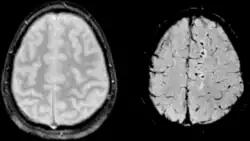

SWI ist ein Magnetresonanztomographie-Verfahren. Sie benutzt flusskompensierte, räumlich hochaufgelöste 3D-Gradientenechosequenzen (GRE-Sequenz) in Einzel- und Multiechotechnik[1] unter Ausnutzung der unterschiedlichen magnetischen Suszeptibilitäten der verschiedenen Gewebe. Diese Unterschiede führen zu einer Phasendifferenz (phase) und bewirken einen Signalverlust (magnitude). Es kommt kein Kontrastmittel zum Einsatz. Mit der Kombination der Signal- und Phasenbilder wird ein erweitertes Kontrastsignalbild erzeugt, welches venöses Blut, (Hirn-)Blutungen und Eisenablagerungen wie Hämosiderin darstellen kann.

Die Bildgebung von venösem Blut mit SWI wird als Blut-Sauerstoff-abhängige Bildgebung (BOLD, blood-oxygen-level dependent) bezeichnet. Venöses (sauerstoffarmes) Blut ist weniger diamagnetisch als arterielles (sauerstoffreiches) Blut. Das Verfahren wurde deshalb ursprünglich als BOLD bezeichnet jedoch später durch den allgemeineren Begriff suszeptibilitätsgewichtete Bildgebung ersetzt. Der Begriff BOLD-Venographie ist heutzutage manchmal noch in Gebrauch. Aufgrund des BOLD-Effektes lässt sich mit SWI das venöse Gefäßsystem gut darstellen.

SWI kann bei Schädel-Hirn-Trauma, bei hochauflösenden Gehirnvenographien und anderen klinischen Anwendungen zum Einsatz kommen. Das zugrundeliegende Prinzip wurde 1997 erstmals publiziert[2] und 2001 umfassend beschrieben.[3]